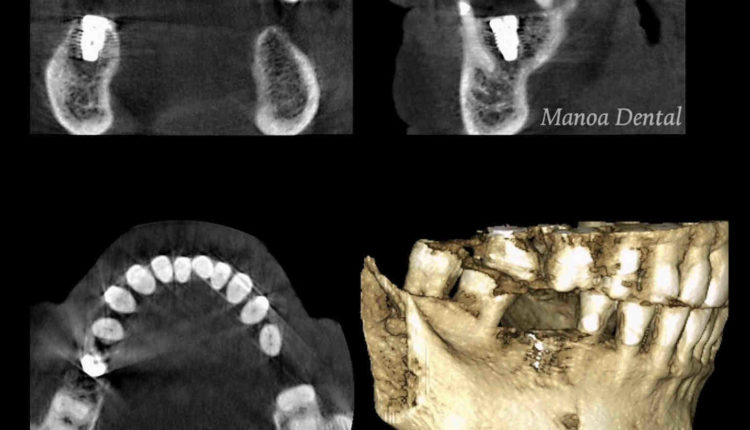

What type of X rays are needed for implant placement?

Cone ray CT is a type of radiography that produces 3D images of dental structures, soft tissues, nerves, and bones. It helps locate dental implants and assesses cysts and tumors in the mouth and face. He may also see problems with gums, tooth roots and jaws.

It takes 1-2 weeks for the initial healing process. However, your implant also needs to be “osseointegrated” with your jaw bone. This means that it attaches completely to the bone, making it a natural part of your mouth.

How long does it take for the implant to Osseointegrate to the bone?

Osseointegration is a term used to describe dental fusion of your natural bone implants successfully. This process can take 3 – 6 months to successfully complete the dental implant.